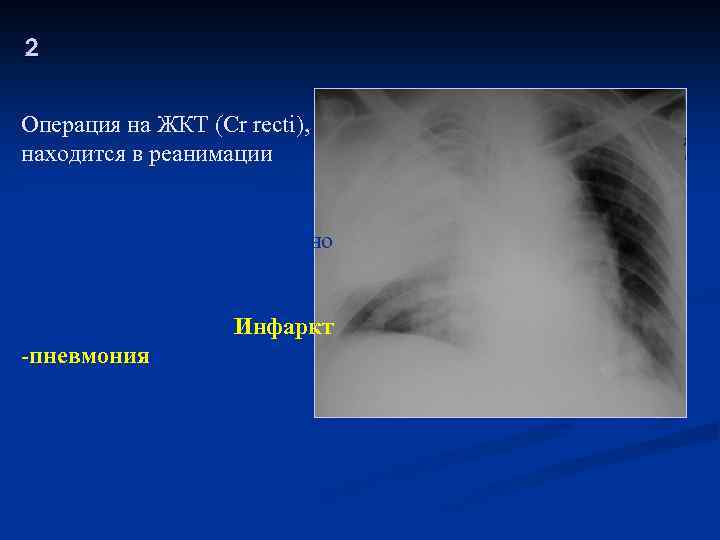

2 Операция на ЖКТ (Cr recti), находится в реанимации Кровохарканье, боли в грудной клетке, лихорадка. Есть сопутствующая сердечно -сосудистая патология. После операции выявлены изменения в легких. Инфаркт -пневмония